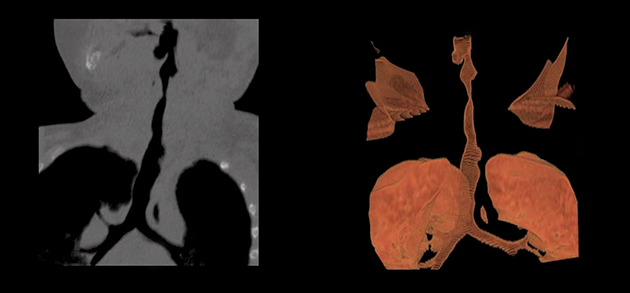

Tomografía computada de detector múltiple de la tráquea en pacientes con MPS.

Cortesía de Dr Grimaldi M. and Dr Parini R. (Monza).